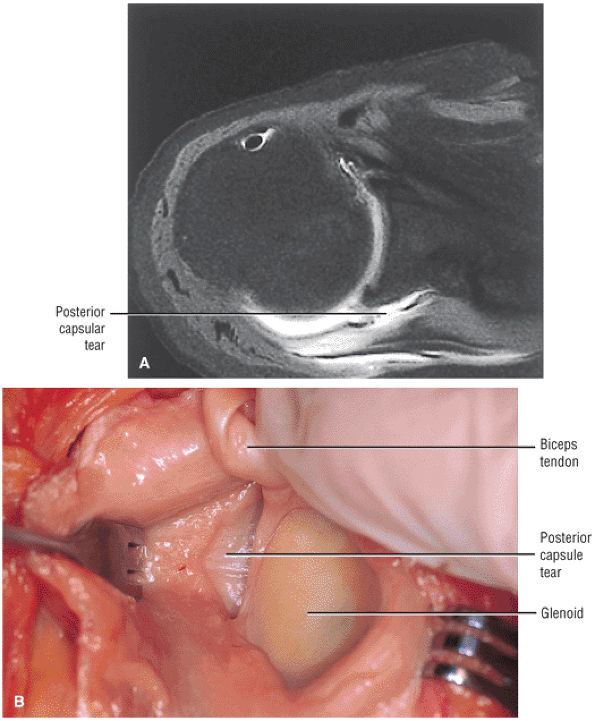

FIGURE 8.102 ● (A) The anterior undersurface of the acromion and the coracoacromial ligament form the coracoacromial arch. The subacromial subdeltoid bursa facilitates the passage of the rotator cuff and proximal humerus under the coracoacromial arch. (B) A superior axial image shows the anterior-to-posterior extent of the coracoacromial (CA) ligament perpendicular to the supraspinatus tendon. The fluid in the subacromial-subdeltoid bursa represents fluid between two serosal surfaces in contact with each other. One serosal surface is contributed by the undersurface of the coracoacromial arch and deltoid, and the other serosal surface is on the bursal side of the cuff.

|

![]() |

FIGURE 8.103 ● Pseudospur. The normal broad attachment of the coracoacromial ligament to the inferior surface of the acromion is shown on (A) T1-weighted coronal oblique and (B) sagittal oblique images. The low-signal-intensity acromial cortex (black arrows) and adjacent coracoacromial ligament and lateral slip of the deltoid attachment (white arrows) give the false impression of a small subacromial spur in the coronal plane. This pseudospur should not be misinterpreted as impingement; otherwise, unnecessary acromioplasties may be performed on patients with a normal coracoacromial ligament attachment and no associated acromial spurs.

-

Impingement syndrome, a clinical diagnosis, is characterized by a range of MR findings from tendinosis to rotator cuff tears.

Intrinsic impingement is associated with shoulder instability.